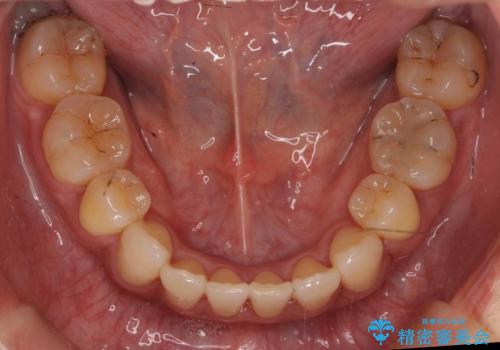

- 前歯の重なりを主訴に来院。

前歯が顔の真ん中に飛び出しているような状態でした。

右上の犬歯が奥深く埋伏していました。

右上以外の3本を抜歯しきちんと並べました。

成人の矯正でしたので、矯正治療前にしっかり必要な歯周病治療を行い、状態が改善してから開始しました。

前歯も引っ込み、口が閉じやすくなりました。